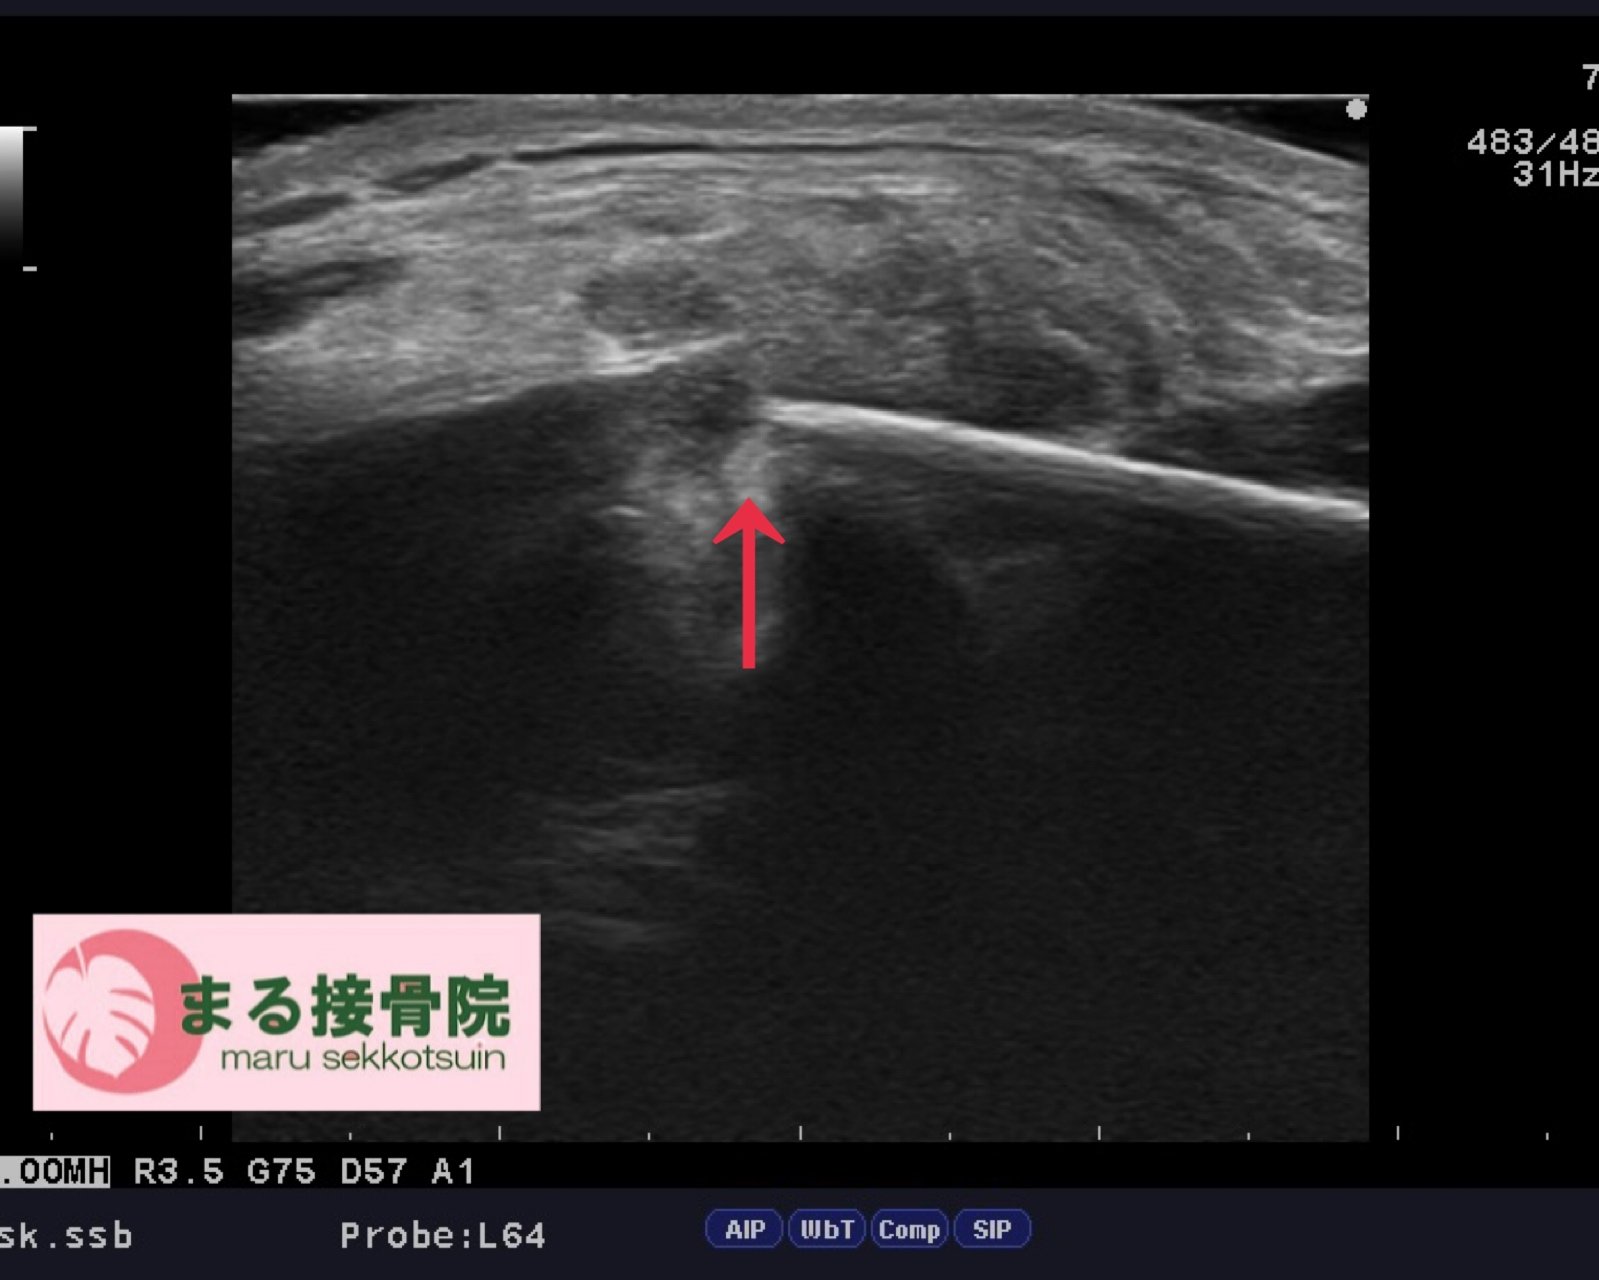

雨の日、バイクに乗っていた際にマンホールの上でタイヤが滑り転倒。

左肩を強く地面に打ちつけ、腕が上がらなくなったとのことでご来院されました。

歩行姿勢や肩の可動域を確認したところ、動きにぎこちなさがあり、骨折の疑い。

すぐにエコー検査を実施した結果、**「鎖骨骨折」**が確認されました。